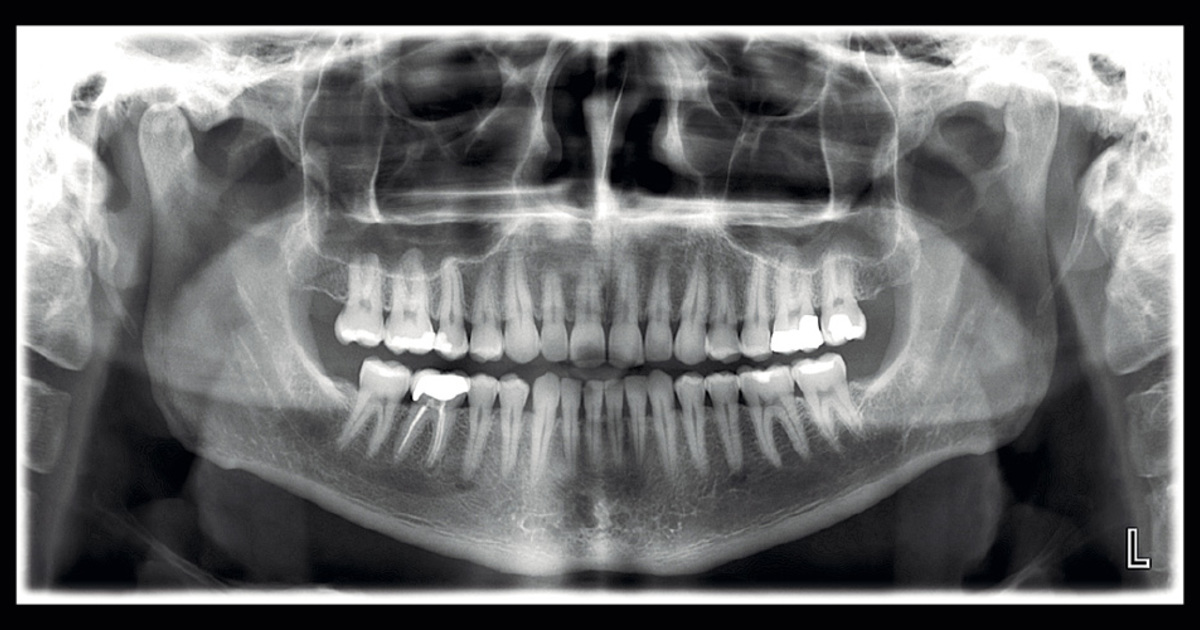

A panoramic radiograph is a panoramic scanning dental X-ray of the upper and lower jaw. It shows a two-dimensional view of a half-circle from ear to ear.

The X-rays use small amounts of radiation. Panoramic X-rays show a broad view of the jaws, teeth, sinuses, nasal area, and temporomandibular (jaw) joints. These X-rays show problems such as impacted teeth, bone abnormalities, cysts, solid growths (tumors), infections, and fractures